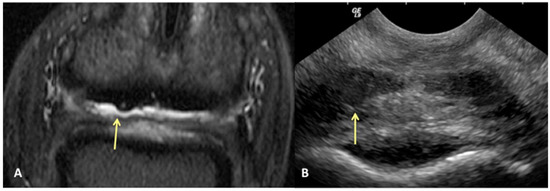

Results of sensitivity, specificity, and accuracy for comparisons of the findings of the DDFT, CSL, and navicular bursa are listed in Table 2. The low number of distal interphalangeal joint collateral ligament abnormalities resulted in low power for the statistic calculation, but prevalent findings are reported below. Ultrasound had the highest sensitivity for detecting enlargement and fiber damage of the dorsal aspect of the DDFT compared to identification of dorsal tearing of the DDFT on MRI, with a sensitivity of 85%, but it was less specific (60%) (Figure 1). Ultrasound was the least sensitive versus MRI to detect displacement (sensitivity 35%) of the CSL but was most specific for this finding (81%). Ultrasound also had a low sensitivity for detecting enlargement of the CSL (42%) but a specificity of 78% (Figure 2). Similarly, ultrasound was also less sensitive to detecting navicular bursa proliferation with a sensitivity of 47% but had higher specificity (78%) (Figure 3).

Figure 2. Transverse proton dense MR image (A) and corresponding transverse ultrasound image (B) of the collateral sesamoidean ligament. Palmar is on the top of the image, dorsal is on the bottom of the image, lateral is on the left. There is diffuse (mild) enlargement of the ligament (yellow arrows), positively identified with MRI and ultrasound.